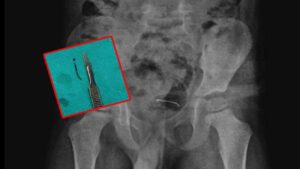

Bitlis'te, 5 yaşındaki bir çocuk oyun oynarken toplu iğne yuttu. 9 ay sonra şiddetli ağrılar yaşayan çocuk hastaneye götürüldü. Yapılan...